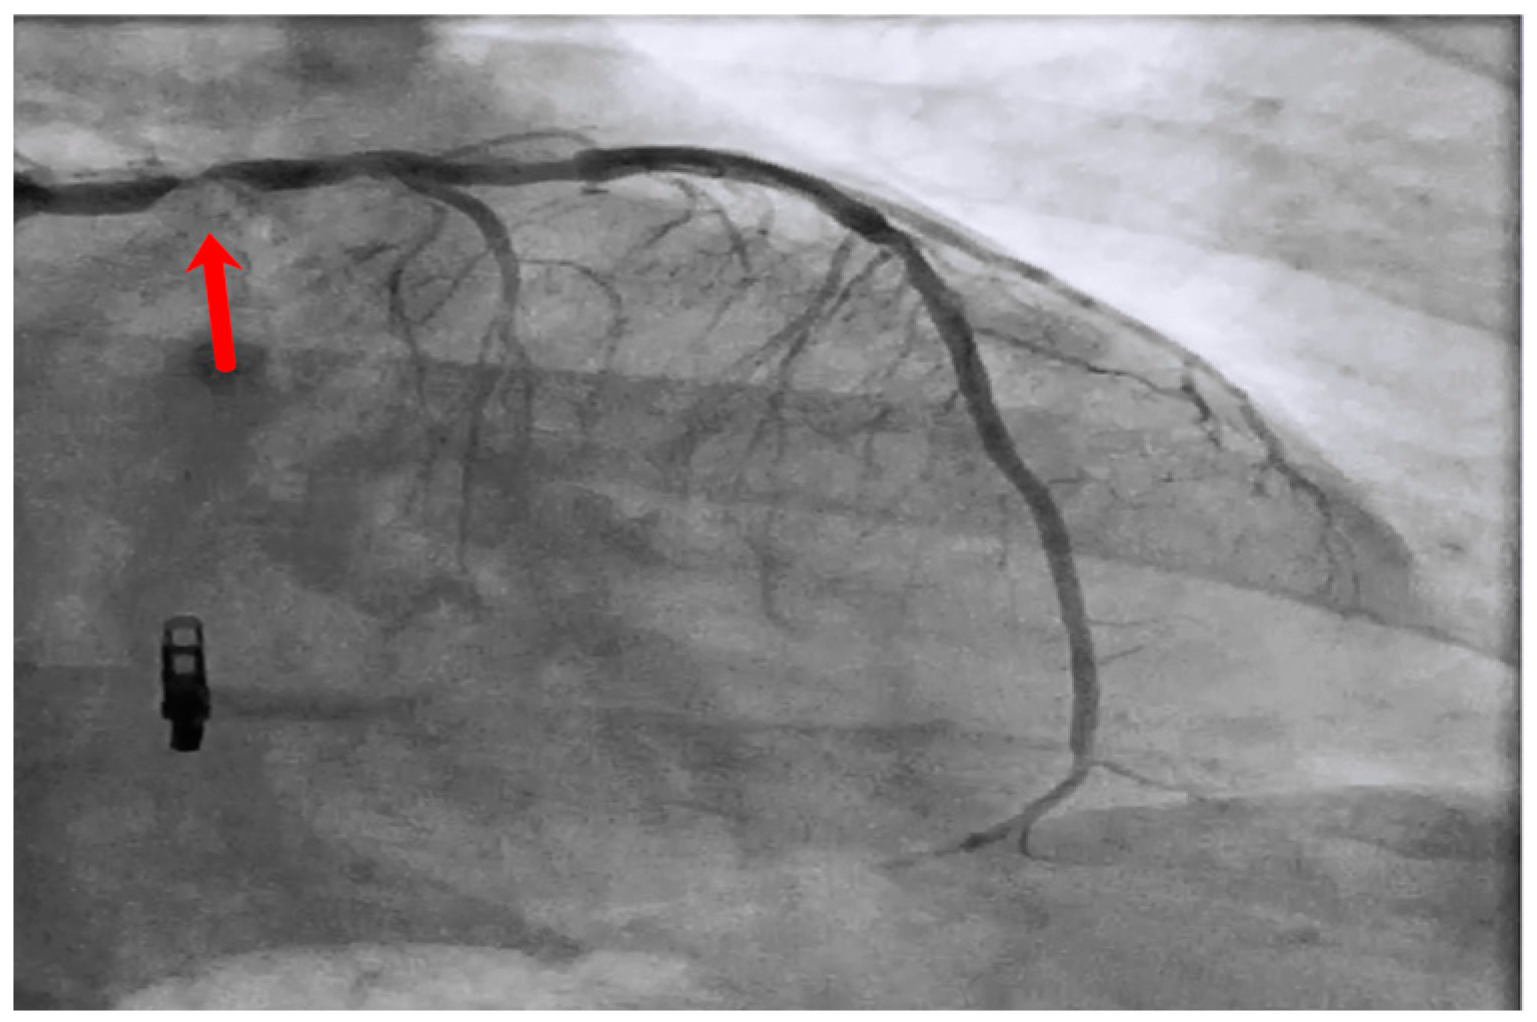

Figure 2.

Left main stem (red arrow) in-stent restenosis.